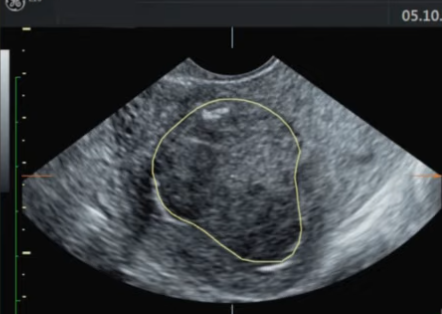

![]() 治疗进行中....

她的月经是正常的 这是一个叫Selva的医生在网上发表的第一例HIFU治疗子宫肌瘤的故事 《My first HIFU patient with fibroids》 临床结果的预测